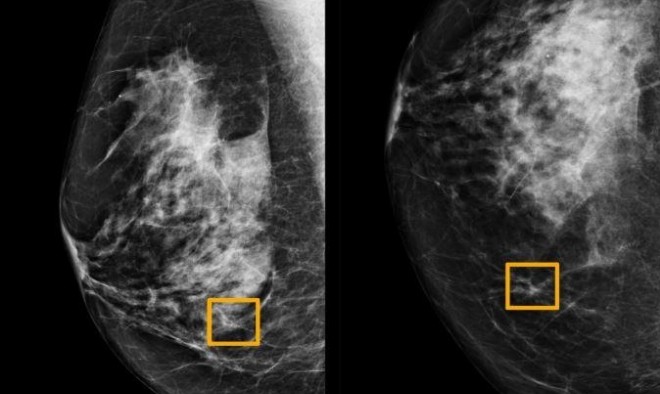

كشف باحثون عن نظام ذكاء اصطناعيّ في "جوجل" يمكن له أن يساهم في اكتشاف الإصابة بسرطان الثّدي لدى النّساء، بدقّة مماثلة لدقة خبراء الأشعة، كما أظهر كفاءة في تقليص الأخطاء في مقارنة تصوير الثدي بالأشعّة السّينيّة.

وأظهرت الدراسة أن نظام الذكاء الاصطناعي تمكن من تحديد الإصابة بالسرطان بدرجة مماثلة لدقة خبراء الأشعة، في حين خفض عدد النتائج الإيجابية الخاطئة بواقع 5.7 في المئة في المجموعة الموجودة في الولايات المتحدة وبنسبة 2.1 في المئة في تلك الكائنة في بريطانيا. وخفض كذلك النتائج السلبية الخاطئة، التي صنفت الاختبارات خطأ على أنها طبيعية، 9.4 بالمئة في المجموعة الأميركية و2.7 بالمئة في المجموعة البريطانية.